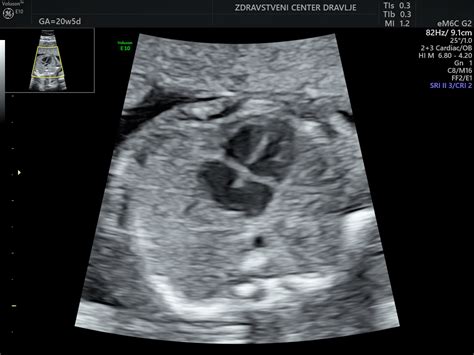

Med pregledi v času pred porodom lahko ginekolog po potrebi uporabi tudi ultrazvok. S pomočjo ultrazvoka lahko ugotovi, ali posteljica še vedno v celoti opravlja svojo funkcijo, se pravi, ali otroka še vedno oskrbuje z vsem potrebnim. Ginekolog lahko oceni tudi verjeten datum poroda. Če se porod pričakuje kmalu in če kardiotokografija (CTG) jasno pokaže, da že imate kratke, neredne popadke, je morda smiselna indukcija poroda. Odločitev o indukciji je odvisna od več dejavnikov, vključno z otrokovim položajem in vitalnimi znaki, ki kažejo, ali je otrok slučajno pod hudim stresom. Obstajajo naravni, blagi načini za sprožanje poroda, na katere se maternica običajno odzove pozitivno, otroka pa spodbujajo, da svojo glavico pomakne navzdol proti medeničnemu obroču, ko bo pravi čas za to.

Pri vsakem pregledu nosečnice se lahko velikost in s tem rast ploda ocenjuje z meritvijo razdalje od simfize do vrha maternice. Ta metoda omogoča spremljanje napredka nosečnosti. Z abdominalnim ultrazvokom lahko ocenimo telesno težo, posamezne plodove parametre, njegovo lego, vstavo, položaj, držo, posteljico, plodovnico in steno maternice. Z vaginalnim ultrazvokom pa lahko izmerimo dolžino in širino materničnega ustja, oddaljenost posteljice od notranjega materničnega ustja, parametre medenice pri nosečnici ter spuščanje glavice oz. medenice ploda glede na interspinalno črto.

Za oceno plodove teže je na voljo več formul. Slovenci najpogosteje uporabljamo formule srednjeevropskih avtorjev. Ocena teže je odvisna od same formule in različnih parametrov, kot so obseg glavice, prečni premer glavice, obseg trebuha, dolžina stegnenice, obseg prsnega koša, obseg stegna, razdalja med ličnicami in volumen ledvic. Te natančne meritve pomagajo pri spremljanju dobrobiti ploda in pripravi na porod.